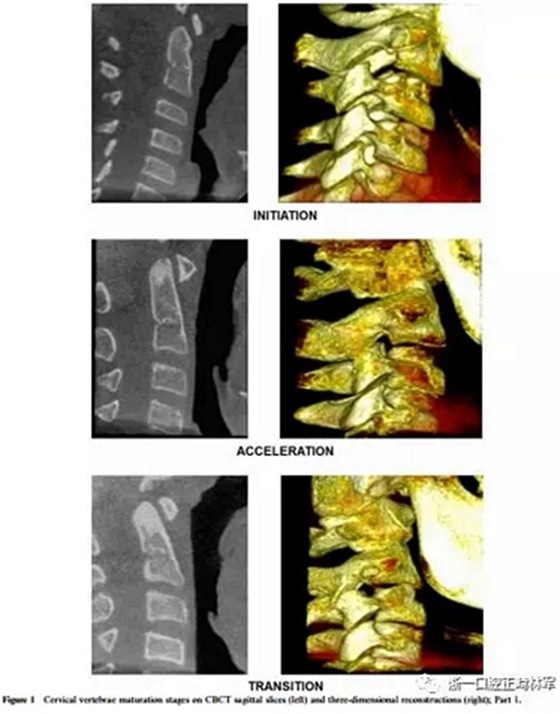

將CBCT三維重建和矢狀切片隨機(jī)分組,并使用軟件OsiriX®(The Osirix Foundation,Geneva,Switzerland)評(píng)估兩次。這些圖像在MacBook Pro(Apple Computer Inc.,Cupertino, CA)。使用OsiriX軟件,通過使用三維成像技術(shù),從醫(yī)學(xué)文件中的數(shù)字成像和通信獲得三維圖像重建。通過多平面重組獲得的矢狀切面是通過將光標(biāo)定位在沿中腭縫線和前鼻棘中心的線上來選擇的。為了避免視疲勞,每天只評(píng)估20幅圖像。評(píng)估分階段進(jìn)行,每次選擇一種展覽模式,第一次和第二次。CBCT圖像在昏暗的房間里,在具有亮度和對(duì)比度恒定特征的屏幕上進(jìn)行解讀,允許利用軟件的縮放,亮度和對(duì)比度工具來增強(qiáng)診斷。每個(gè)展覽模式的圖像解讀最短時(shí)間為15天。在第一次評(píng)估后1個(gè)月,考慮到3D重建和矢狀切片(圖1和圖2),讀片員再次讀片,獲取72條記錄。

椎骨C2,C3和C4的分類方法分為六個(gè)階段,可以描述如下:

1、初期(頸椎成熟指數(shù)-1)

這對(duì)應(yīng)于青春期生長(zhǎng)噴發(fā)(PGS)的初始階段,其中預(yù)期有80-100%的增長(zhǎng)。椎骨的下邊界是平坦的。在C3和C4的上邊界有一個(gè)從后向前的斜坡。

2、加速期(頸椎成熟指數(shù)-2)

這個(gè)階段接近PGS峰值,預(yù)計(jì)增長(zhǎng)率為65-85%。椎骨C2和C3的下邊界呈現(xiàn)一個(gè)小的凹陷,這在C4上仍然是平坦的。 C3和C4的體部呈矩形。

3、過渡期(頸椎成熟指數(shù)-3)

這對(duì)應(yīng)于個(gè)人的高峰增長(zhǎng),預(yù)計(jì)增長(zhǎng)25-65%。 C2和C3的邊界呈現(xiàn)出不同的凹陷,這在C4上很微小。椎骨C3和C4的體部是矩形的。